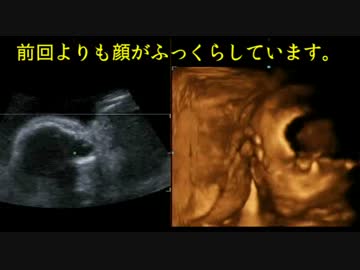

【エコー】赤ちゃん(22週)